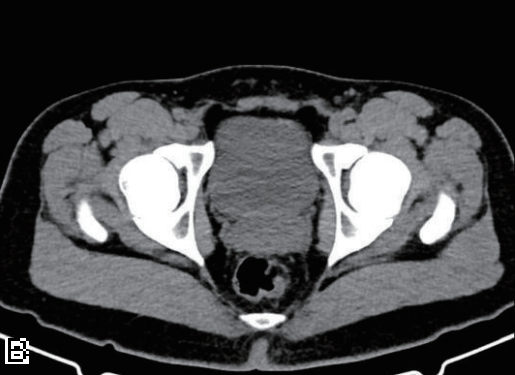

优化后确诊典型病例分享

基础信息:患者女,48岁,尿血吸虫虫卵阳性,偶左下腹隐痛,血清抗体1∶256,尿常规红细胞(+);采用定制CT方案(肾上极至膀胱下缘,100 kV/80 mA,术前40分钟服800 ml水充盈膀胱)。

影像表现与诊断价值:CT平扫示膀胱前壁增厚(图2A),左肾盂轻度扩张(1.8 cm,图2B),肾盏增宽,薄层重建及功能评估识别可逆性肾损伤。左输尿管下段管壁增厚(3 mm)、节段性狭窄(1.5 cm长,最窄1.5 mm),近端轻度扩张(图2C),延迟期清晰显示病变、减少肠道干扰。

干预与预后:吡喹酮治疗,1个月后复查示输尿管狭窄减轻、肾盂积水消失,肾功能恢复,精准诊断避免不可逆损伤。

图2

A:3 mm层厚泌尿系CT平扫轴位示膀胱前壁增厚约6 mm(箭头);

B:左肾盂轻度扩张(1.8 cm)(箭头),肾盏增宽;

C:左输尿管下段管壁增厚(3 mm)(箭头)、节段性狭窄(1.5 cm长,最窄1.5 mm)